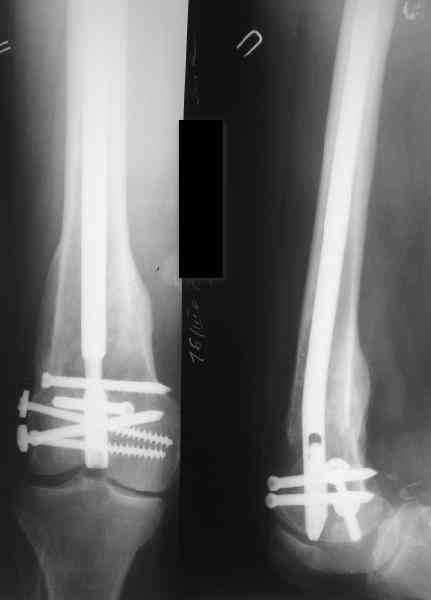

Да, действительно красивый клинический пример: виден вальгус до операции и последующая коррекция углового смещения на "полярах". Я так понимаю, что в вашей клинике есть возможность использовать различные фиксаторы. Почему не использовали DFN? Спицы какие используете? Киршнера или Илизаровские? С виду очень тонкие...

> фиксаторы. Почему не использовали DFN?

В смысле, почему не ретроградно? При дистальных переломах или их последствиях и так с коленом может быть не все в порядке, и чрессуставное введение гвоздя состояние колена как имнимум не улучшает. Поэтому наиболее дистальные как раз штифтуем обычно антеградно. Хотя 20-25% бедер штифтуем ретроградно, но более проксимальных.

А на DFN свет клином не сошелся, мы используем отечественные штифты (MetaDiaFix, "ЦИТО"), которые можно вводить и ретроградно (4 винта), кроме того, в качестве ретроградного бедренного замечательно подходит большеберцовый гвоздь диаметром 12 мм.